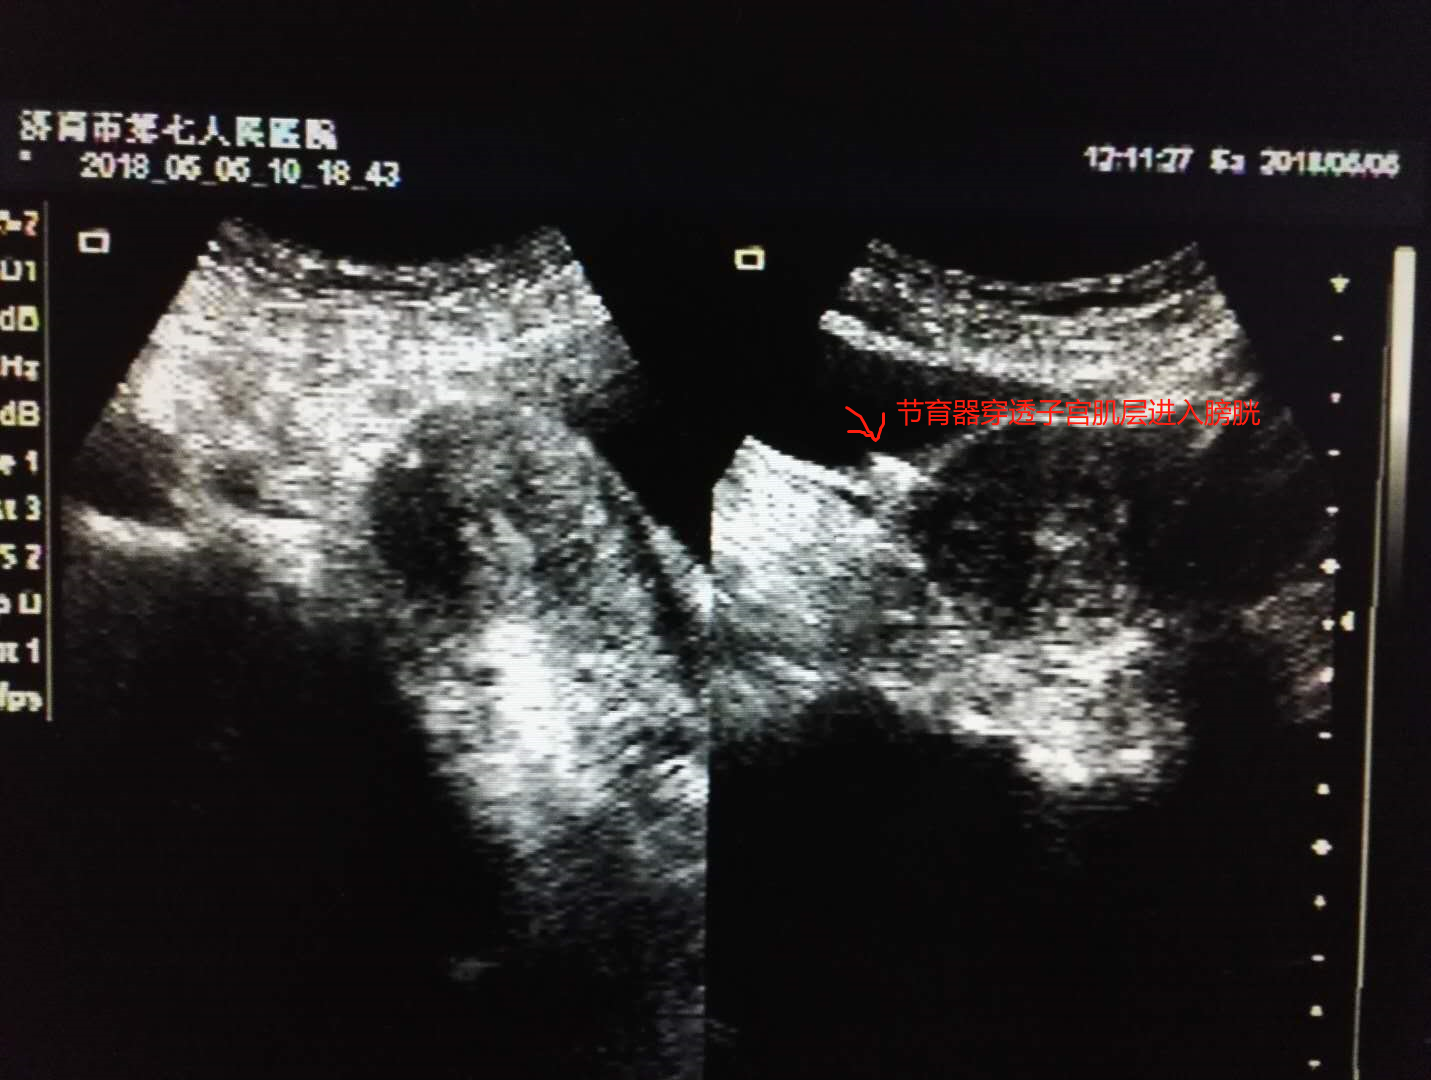

李女士根据妇科医生建议来到超声室,超声大夫也是第一次碰到这种案例,经过科室会诊后,诊断李女士为节育器宫底肌层嵌顿并部分穿破子宫向外延伸至膀胱壁,也就是说李女士的“环环”就是个不安分的“环环”。随后,李女士住院进行了节育器取出术加膀胱修补术,“环环”直接被请出了宫……